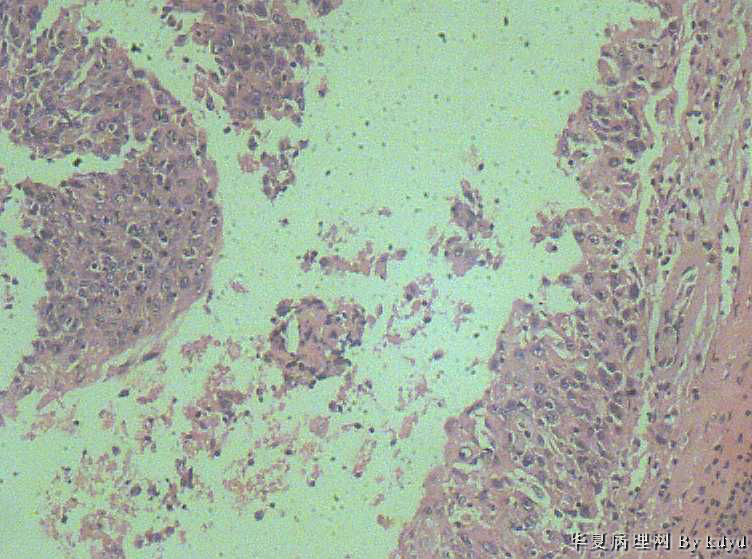

B3997左乳肿瘤--浸润性导管癌?

37岁,女。左侧乳腺肿块发现5个多月,伴隐痛。

手术见:肿块与周围组织分界不清,无明显包膜。

大体:不整形组织大小约3.5*35*2CM,未见明显包膜。质较软,切面浅黄色,一侧见一小囊腔直径约0.8CM囊壁较粗糙。

标签:乳腺浸润性导管癌 原位癌

浸润性乳腺导管癌?

IDC

乳腺浸润性导管癌

囊壁内大量炎细胞浸润,囊壁被覆细胞有明显异型,可见核分裂,考虑癌,不知有无陷阱

浸润性导管癌

应该是个浸润性导管癌

但是,片子质量欠佳

不太敢直接下

诊断乳腺浸润性导管癌确实有些担心,制片质量确实要提高,制作优良的切片,是正确诊断的前提。